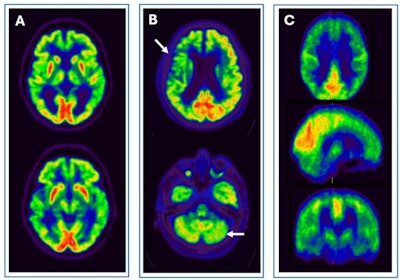

![Pitfalls and artifacts in [F-18] FDG PET imaging. (A) Scan of a patient with central nervous system drug interference shows cortical hypometabolism that could mimic an AD pattern, but with thalamic hypometabolism characteristic of this interference. (B) Scan of a patient with a right frontoparietal ischemic antecedent (arrow), showing a diaschisis of the contralateral cerebellum (arrow) due to disruption of the corticospinal tract. (C) An example of a PET scan with motion artifacts.](https://img.auntminnieeurope.com/files/base/smg/all/image/2025/02/2025_02_13_mol_insider_Figure_5.67ad30bfe2686.png?auto=format%2Ccompress&fit=max&q=70&w=400) Pitfalls and artifacts in [F-18] FDG PET imaging. (A) Scan of a patient with central nervous system drug interference shows cortical hypometabolism that could mimic an AD pattern, but with thalamic hypometabolism characteristic of this interference. (B) Scan of a patient with a right frontoparietal ischemic antecedent (arrow), showing a diaschisis of the contralateral cerebellum (arrow) due to disruption of the corticospinal tract. (C) An example of a PET scan with motion artifacts.

Pitfalls and artifacts in [F-18] FDG PET imaging. (A) Scan of a patient with central nervous system drug interference shows cortical hypometabolism that could mimic an AD pattern, but with thalamic hypometabolism characteristic of this interference. (B) Scan of a patient with a right frontoparietal ischemic antecedent (arrow), showing a diaschisis of the contralateral cerebellum (arrow) due to disruption of the corticospinal tract. (C) An example of a PET scan with motion artifacts.